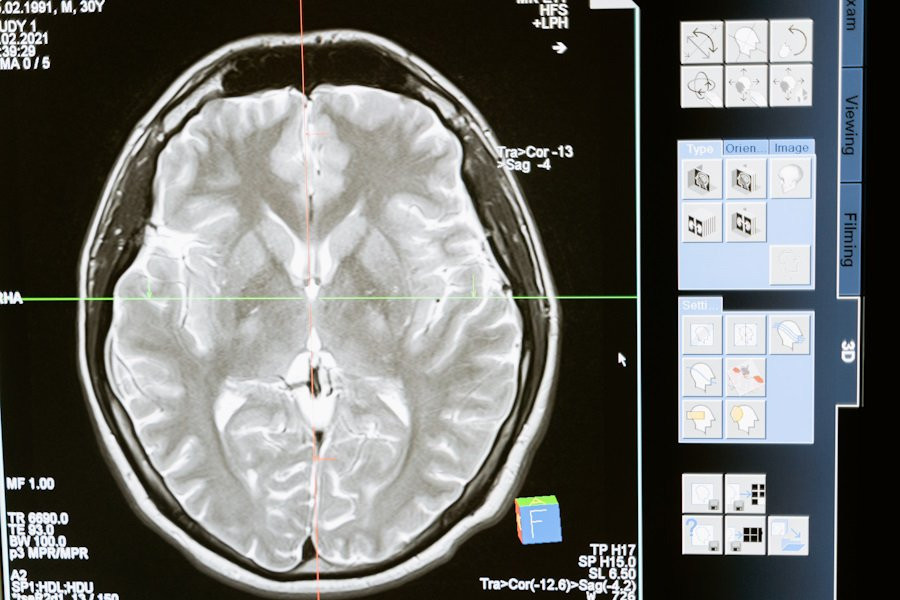

Фото из открытых источников

Согласно сообщению об исследовании, опубликованному на портале Science Robotics, ученые из Harvard Medical School (Boston, США) успешно разработали двуручного эндоскопического хирургического робота, который может значительно снизить инвазивность операций на головном мозге.

Используя этого робота, управляемого джойстиком, исследователи демонстрировали эффективность в выполнении задач, аналогичных этапам резекции опухоли головного мозга.